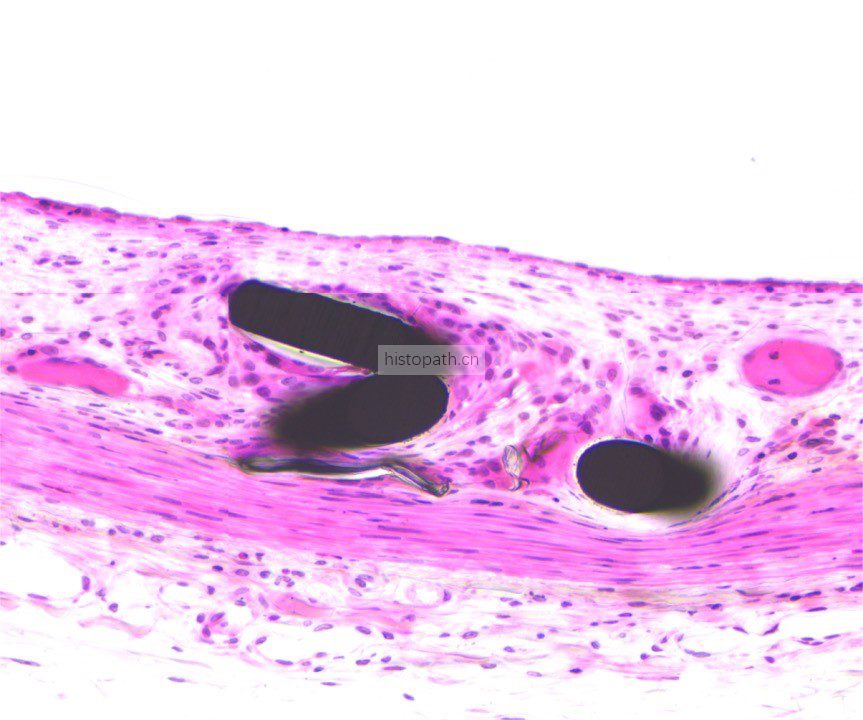

使用德国EXAKT切磨系统进行硬组织切片,特别是对于含有金属这类植入物的组织,是一种精确的组织切片技术。

将包埋好的硬组织树脂块,用EXAKT 硬组织切片机先切一个200um的厚片,然后再通过EXAKT 硬组织磨片机将其磨到20-30um薄片,样本是已经硬组织包埋好的含金属的动物样本。

针对不同的病理阅片指标需求,行HE染色、Masson染色、亚甲基蓝-酸性品红染色、VG染色、Movat染色等。